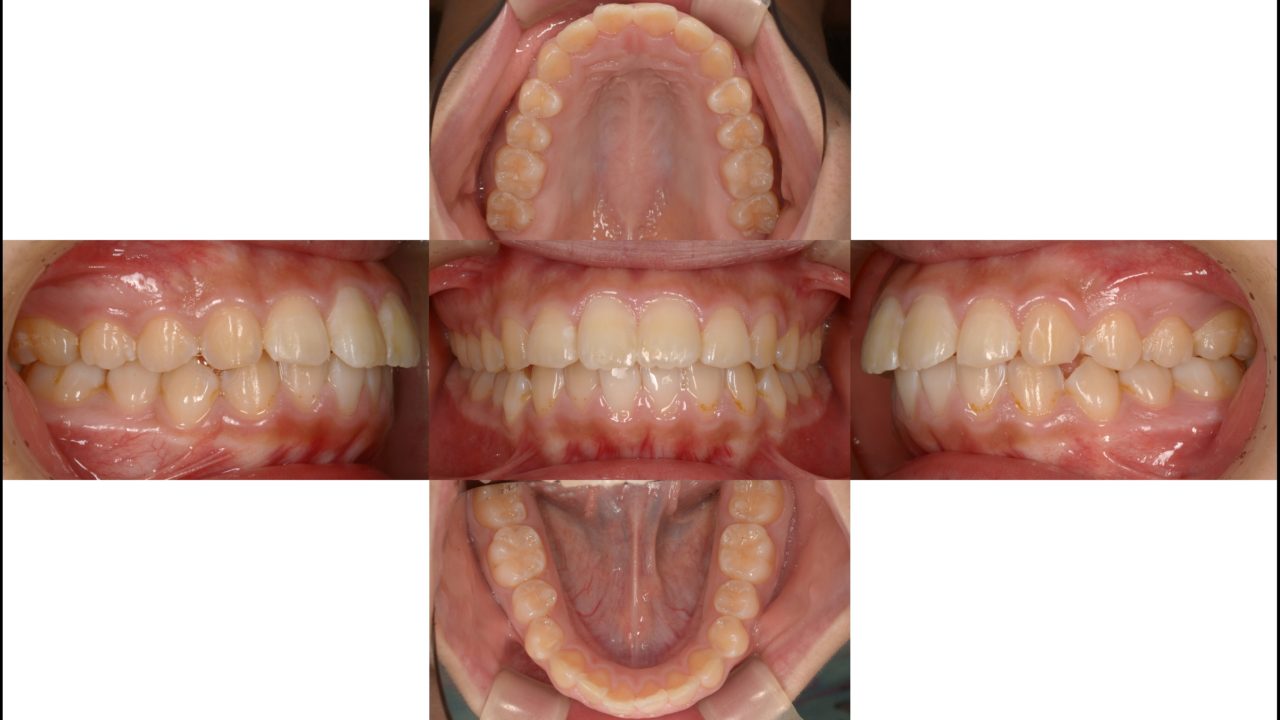

Before

初診 2018.5.12